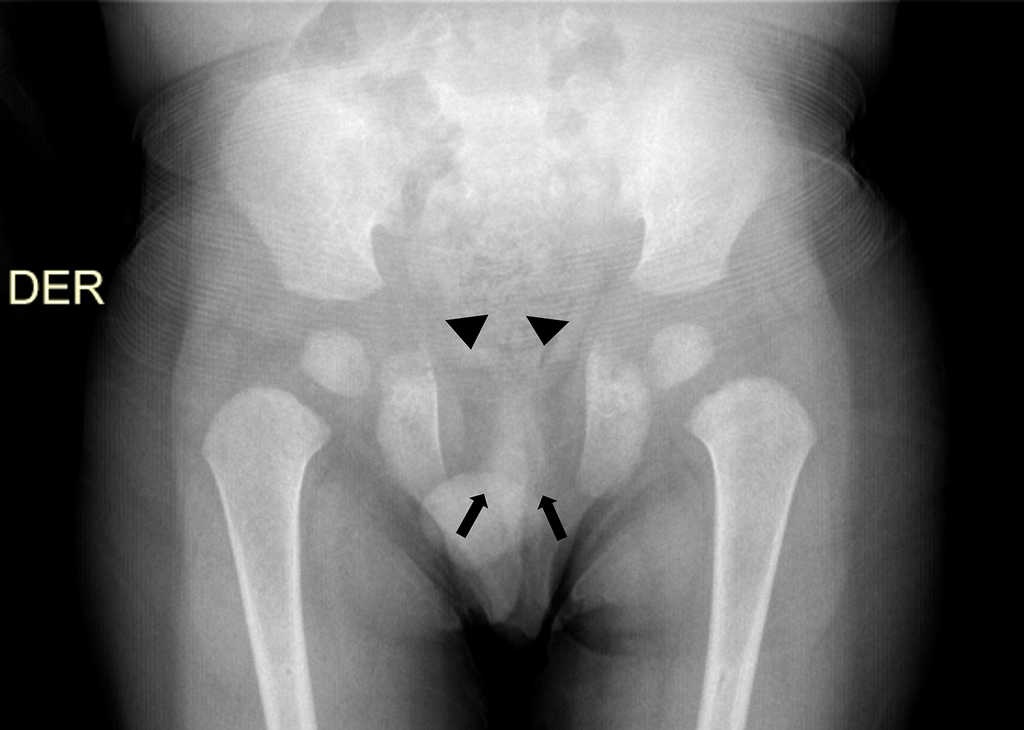

A pesar de su baja prevalencia, se considera necesario el conocimiento de esta entidad por parte del médico radiólogo para realizar un diagnóstico adecuado y oportuno. Por ello, comunicamos el caso de un niño de 3 años que consultó inicialmente por una caída desde aproximadamente 1 metro de altura, con trauma en miembro superior derecho. En la radiografía (Rx) se evidenció una fractura del cóndilo lateral humeral. No obstante, en el examen físico se encontró talla baja, hipertelorismo y alteraciones óseas craneales, consistentes en diastasis de suturas y persistencia de fontanela anterior abierta, además de macroglosia, paladar ojival, dismorfismo dentario (se sospechó diagnóstico de Síndrome de Pierre Marie Sainton en su forma esporádica), ausencia de clavículas y pectus excavatum. La Rx convencional de tórax anteroposterior demostró apariencia triangular del tórax y ausencia congénita de ambas clavículas (fig. 1), mientras que la Rx anteroposterior de pelvis reveló ausencia de osificación de las ramas iliopúbicas y osificación parcial del isquion, con ausencia de las ramas isquiopúbicas (fig. 2). No se ampliaron estudios para detectar anormalidades en el desarrollo óseo de manos y columna vertebral.

*Pelvis

-Retraso en la osificación del hueso púbico, con sínfisis púbica amplia

-Hipoplasia de los alerones ilíacos

-Articulaciones sacroilíacas amplias